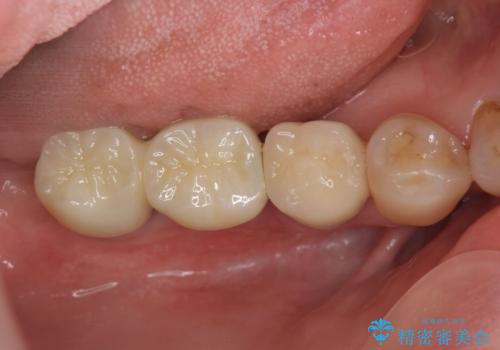

- 「奥歯で噛むと痛い、いつも膿のにおいがして不快、改善してほしい。」と治療を希望され来院されました。

精査した結果、奥歯の根は破折しており抜歯を避けられない状況でした。

咬合力が強く、その他の歯の破折も防ぐために奥歯の咬合機能をインプラントを用いて回復する治療計画を立てます。

- 99万円(インプラント×2・チタンカスタムアバットメント×2・ジルコニアクラウン×2・仮歯×2)費用は治療当時の料金となります